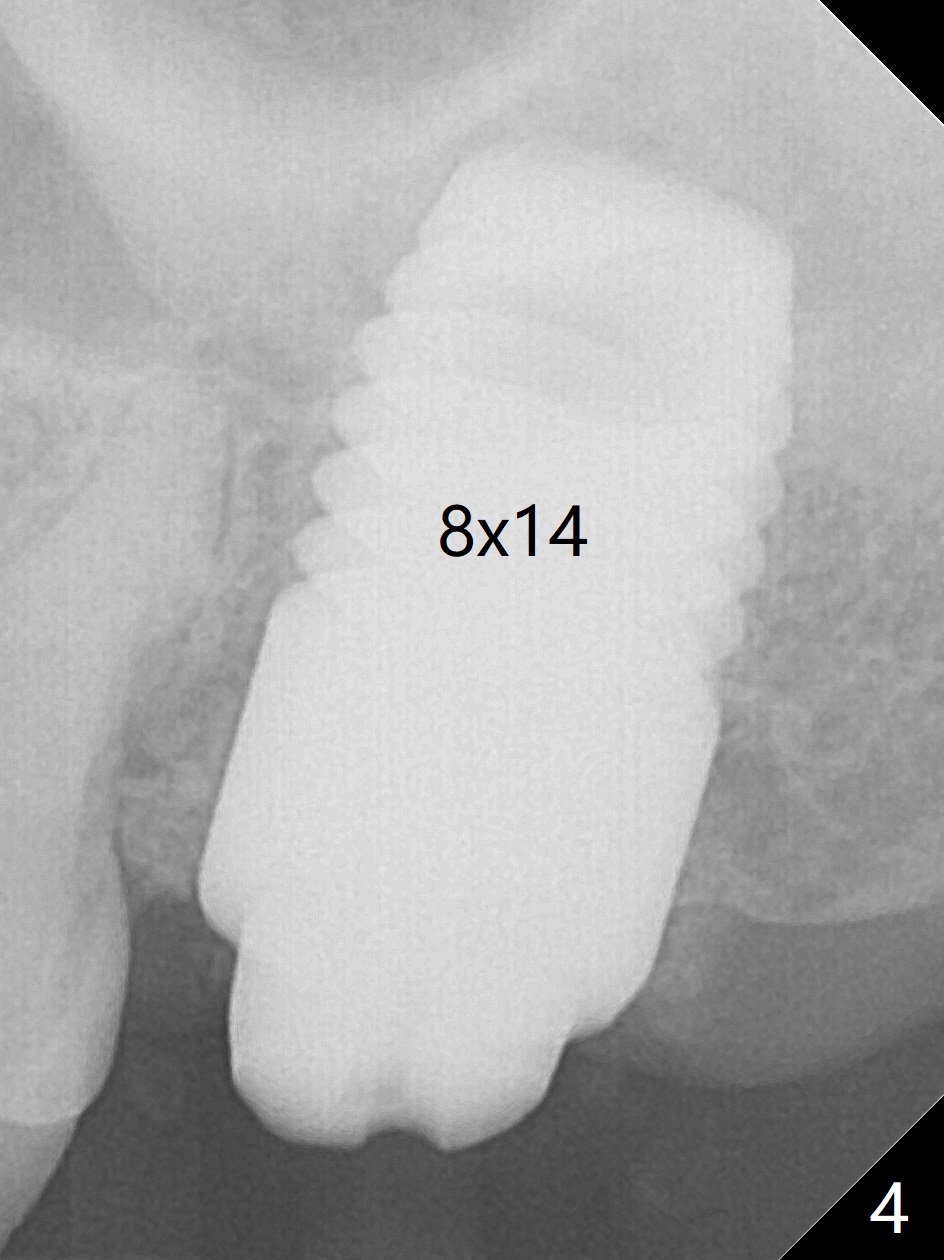

Initially the patient is reluctant to have the crack tooth extracted (Fig.1). Blood drawing for PRF fails. After extraction, the septum is confirmed to be short and thin. The bone density is moderate. When a 3.5 mm drill is being used, the osteotomy perforates into the mesiobuccal socket. A 5x10 mm IS implant achieves minimal stability. As 5.5, 6.0 and 7.0 mm cortical taps are inserted, primary stability is not obtained, as more bone is being removed at the level of the septum. When a 7x17 mm Tatum tapered tap is placed, it looks too small for the socket, as confirmed by measurement of a preop PA (Fig.2). Chronic infection associated with crack syndrome for 2 years may cause bone loss of the socket walls. Since the primary stability of a 8x17 mm tapered tap is not high (Fig.3), a 8x14 mm cylindrical implant is placed (after try in of its dummy one) with > 50 Ncm (Fig.4). The implant engages into the mesial and distal socket walls for stability. A 6x3 mm abutment is placed for an immediate provisional. In spite of difficult manipulation, the sinus membrane remains intact. Vanilla graft is placed for sinus lift and buccal and palatal gaps. Since IS implants are more or less cylindrical and if a 5 mm one does not achieve primary stability, a larger Tatum tapered tap should be tried immediately without using IS cylindrical taps. The patient returns 3 months postop, requesting early restoration before a trip to home country. The provisional has occlusal perforation. Final restoration is cemented nearly 4 months postop (Fig.5,6). The large implant makes the early restoration possible. However there is bleeding on probing palatal 1.5 years post cementation (Fig.7), suggesting palatal thread exposure. Return to Upper Molar Immediate Implant, Prevent Molar Periimplantitis (Protocols, Table), Armaments 6 Xin Wei, DDS, PhD, MS 1st edition 05/07/2018, last revision 05/08/2021